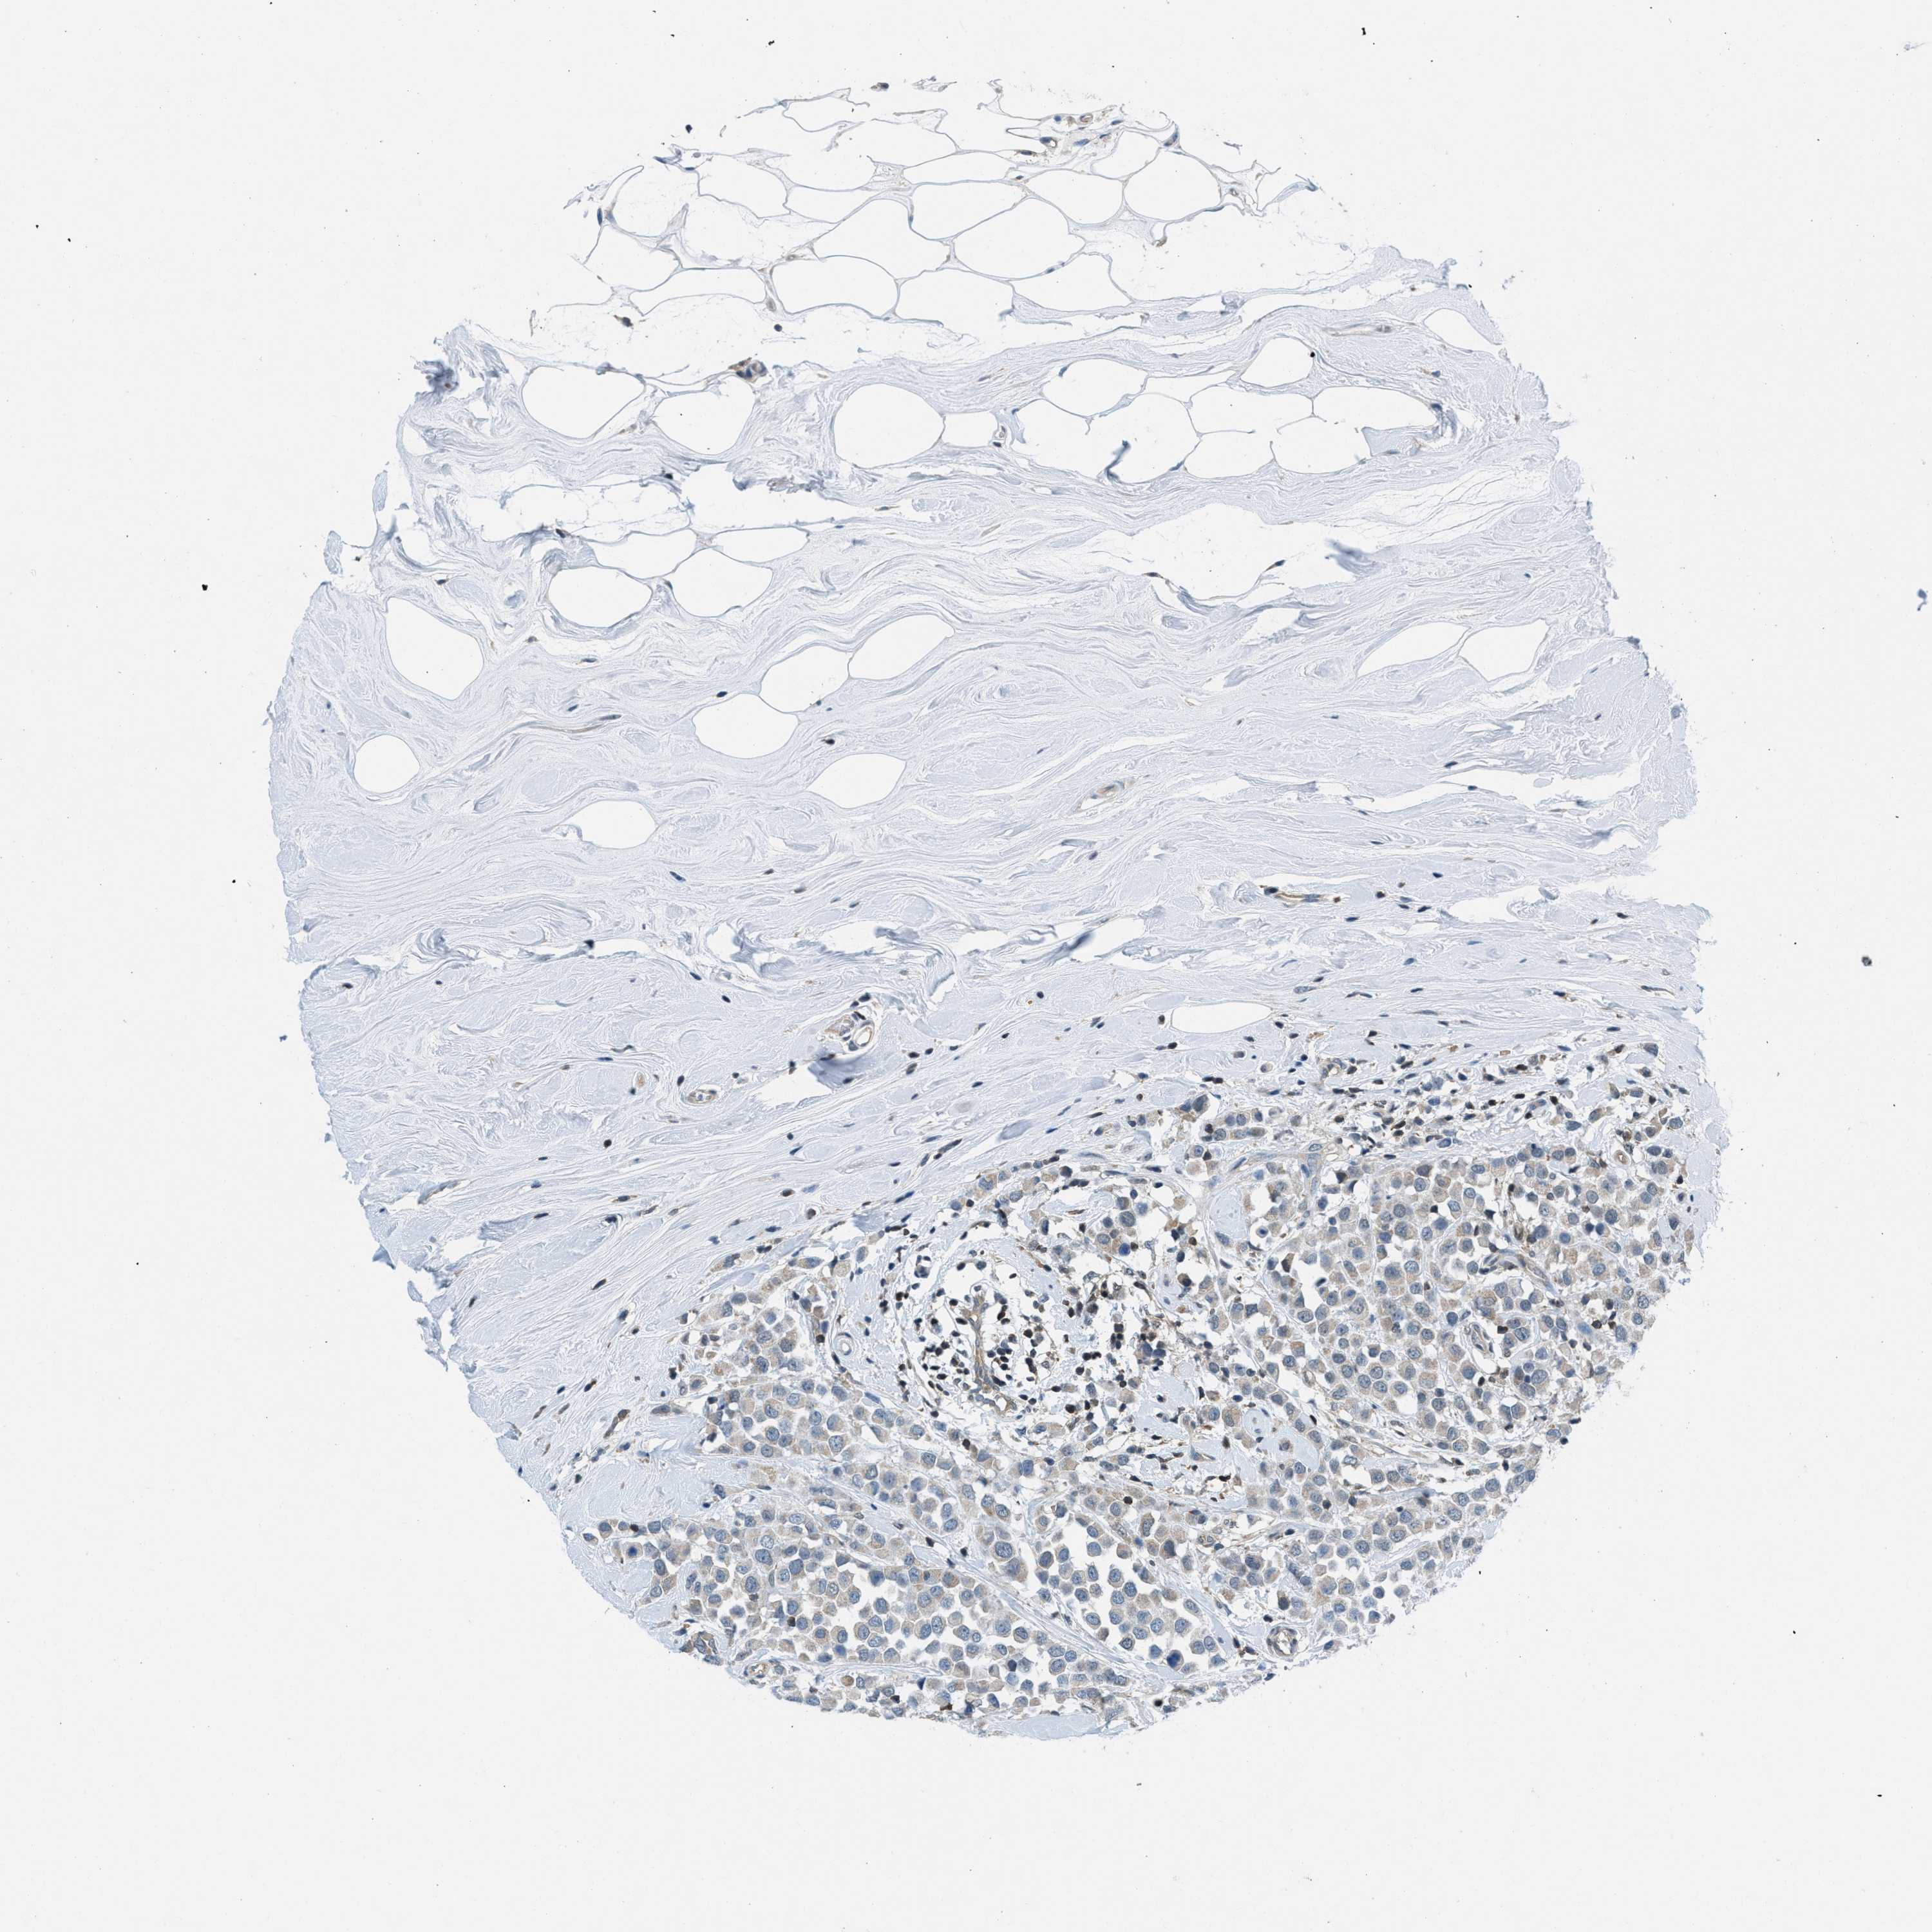

CANCER BREAST CANCER Show tissue menu

BRCA TCGA BRCA VALIDATION PROTEIN EXPRESSION